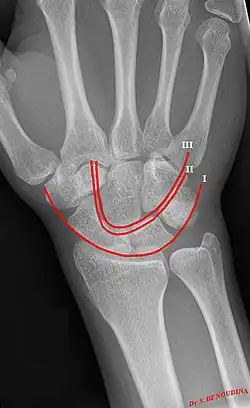

Gilula's lines are three arcs drawn on an AP radiograph of the wrist used to assess the alignment of the carpal bones.[1]

There should be no step-off in the contour of the lines when drawn on a normal wrist.

| First arc | running along the proximal convexity of the scaphoid, lunate and triquetrum |

| Second arc | running along the distal concavities of the scaphoid, lunate and triquetrum |

| Third arc | running along the proximal curvatures of the capitate and hamate |